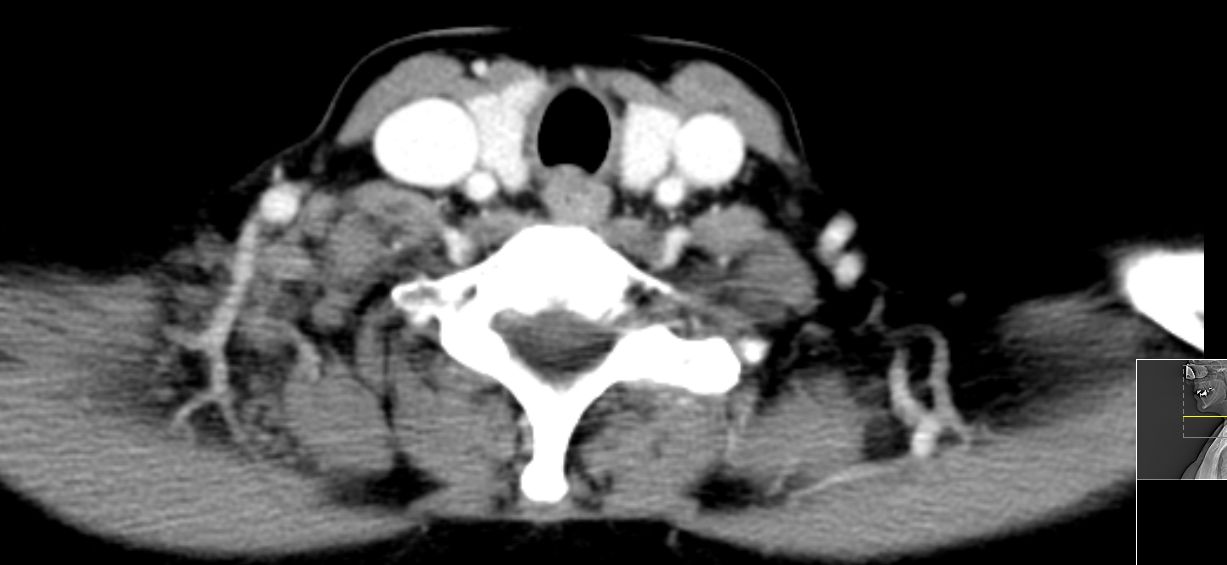

52-jährige Frau, bei der vor einem Jahr ein 15 mm großes invasiv-duktales Mammakarzinom rechts o/iq nach 3 Wochen Letrezol (Adapt-Studie) operiert wurde. Postoperativ ypT1c, ypN0 (0/2 sn), cM0, L1 V0 R0, G2, ER: 6/12, PR: 0/12, HER-2/neu: negativ, Ki-67: 30%, Oncotype DX Recurrence Score 40. CHT: 8 x nabPaclitaxel -> 4 x EC. Dann Bestrahlung der Brust. AHT mit Letrozol. Jetzt palpable Lymphknotenmetastasen supraklavikulär rechts. CT: Die teilweise rechts retroklavikulär hinter der rechten medialen Klavikula und supraklavikulär gelegenen Lymphknotenmetastase hat eine Größe von maximal 2,5 cm. Weiter oberhalb und dorsalseitig sind im rechten unteren Halsdreieck dorsal der rechten Vena jugularis externa konfluierende inhomogene Lymphknoten mit Einzelgrößen bis zu 1,5 cm und einer Gesamtpaketausdehnung bis zu 4 cm sichtbar. | ||